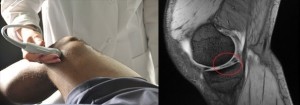

La Risonanza Magnetica al Ginocchio: non solo per gli sportivi

La risonanza magnetica al ginocchio rappresenta il metodo diagnostico per eccellenza nel rilevare patologie, sia di tipo tumorale o degenerativo, alterazioni riguardanti il legamento, il muscolo e le ossa del ginocchio e per identificare lo stato di recupero post operazione.